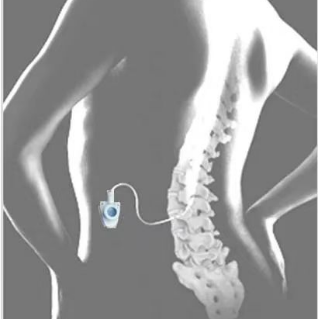

鞘内吗啡镇痛泵植入术(一)

鞘内吗啡镇痛泵植入术,又称“植入式鞘内药物输注系统”,是一种先进的微创介入镇痛技术。它通过将药物直接输送到脊髓周围的脑脊液中,像建立一个“直达疼痛中枢的精准给药通道”,从而高效地控制顽固性疼痛。它真正实现了 “用最小的药量,达到最强的效果,产生最少的副作用”的精准医疗目标,为众多深受顽固性疼痛折磨的患者提供了重返高质量生活的希望,是“舒适化医疗”理念的杰出体现。是目前国际上治疗顽固性疼痛及癌痛的核心技术。

鞘内吗啡本治疗示意图